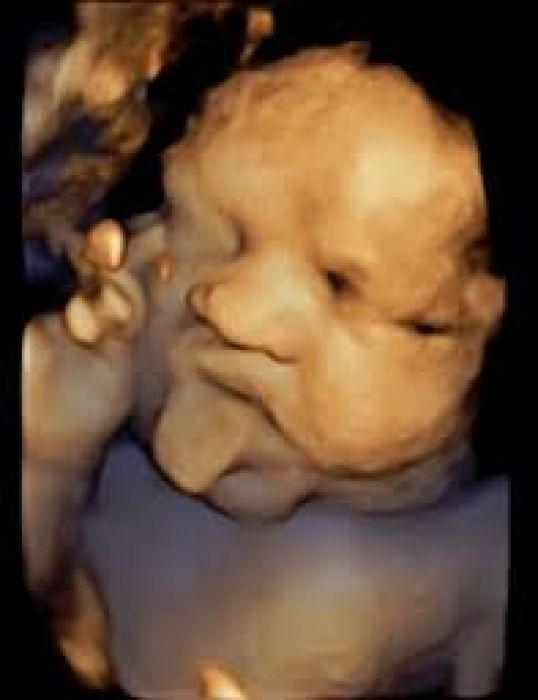

การตรวจอัลตราซาวด์ เพื่อวัดความหนาของน้ำที่สะสมบริเวณต้นคอทารก (NT:Nuchal Translucency) ขณะอายุครรภ์ 10-14 สัปดาห์ ถ้าหนาผิดปกติก็จะมีความเสี่ยงสูงขึ้น ส่วนการตรวจอัลตราซาวด์ในช่วงอายุครรภ์ 18-20 สัปดาห์อาจจะใช้บอกระดับความเสี่ยงได้บ้าง

แหล่งที่มาของภาพ : https://www.bccgroup-thailand.com/